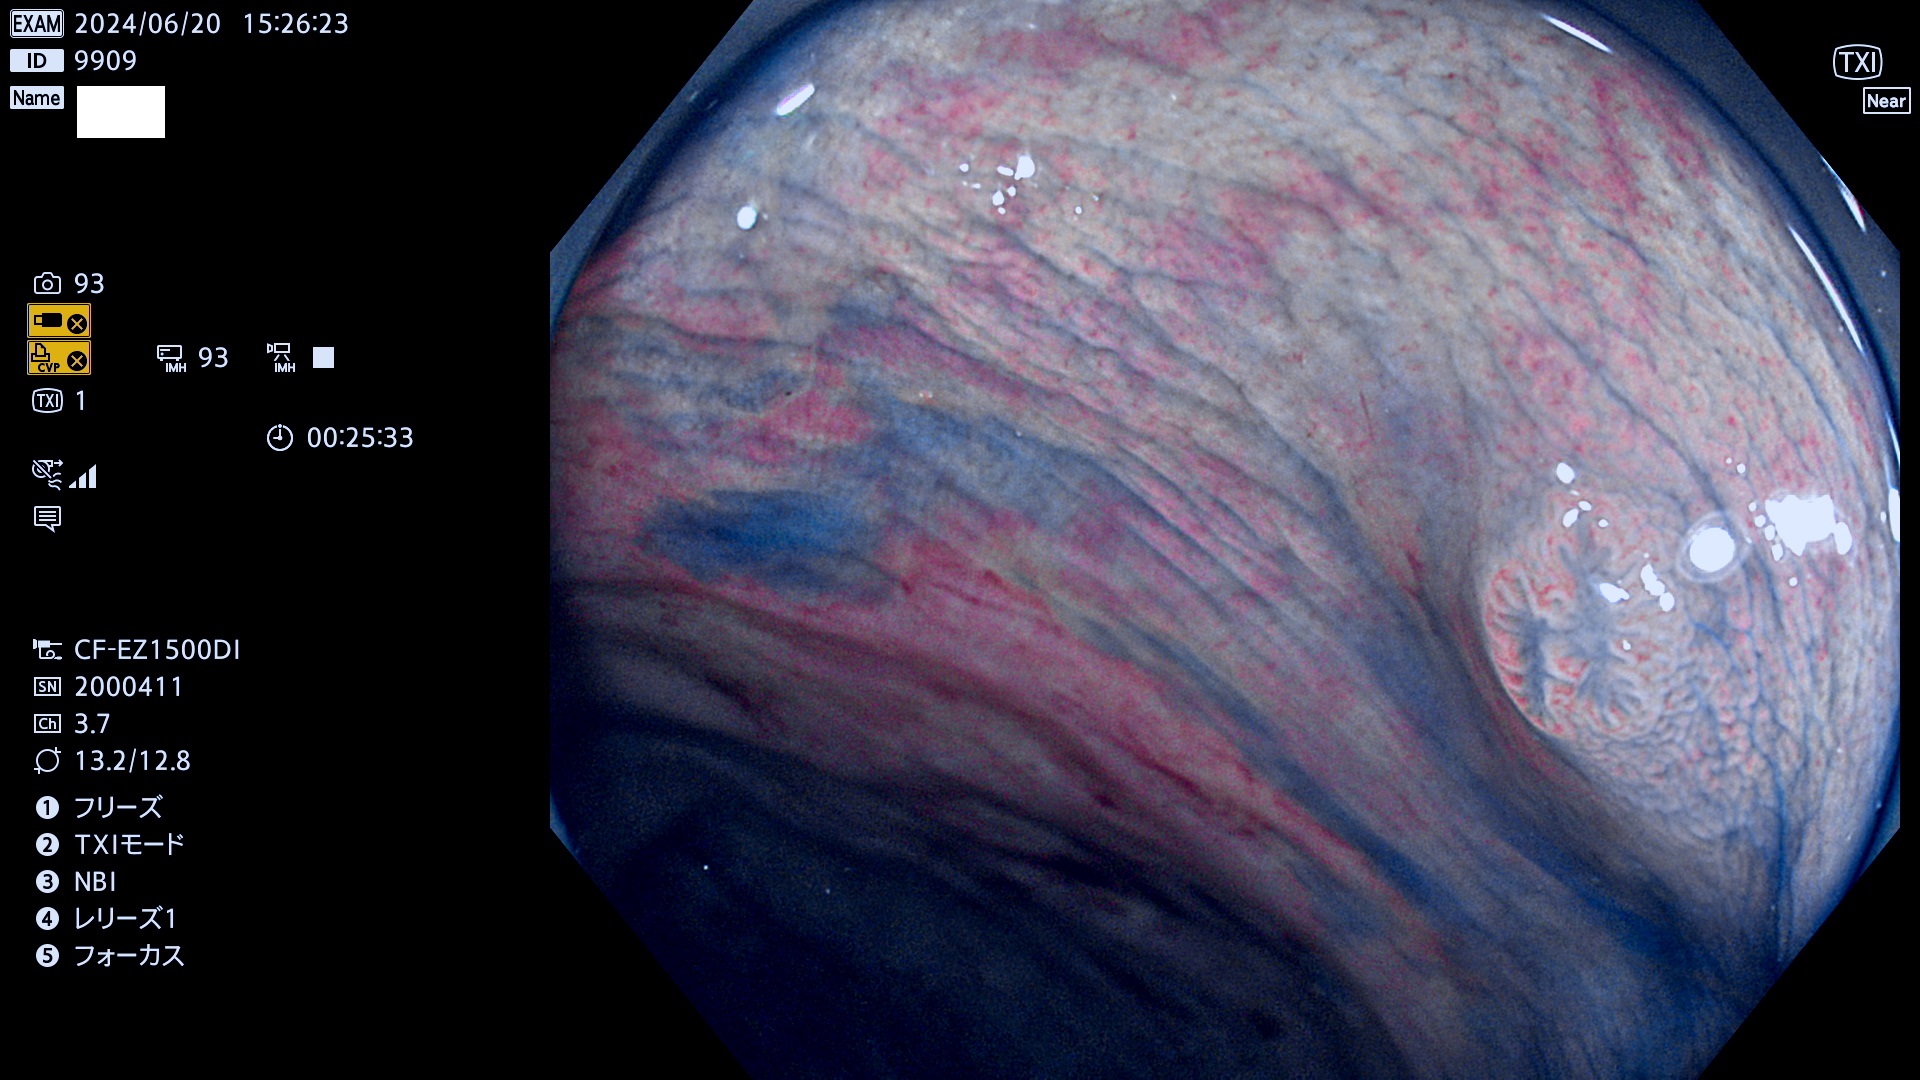

今週のUb、Uc型腺腫

完全に平坦な物をUb、陥凹している物をUcと呼びます。最も発見が難しく危険な病変です。

抽出の対象期間 2024年6月20日〜6月24の5日間(40件の検査)6件 (6/40=15%)